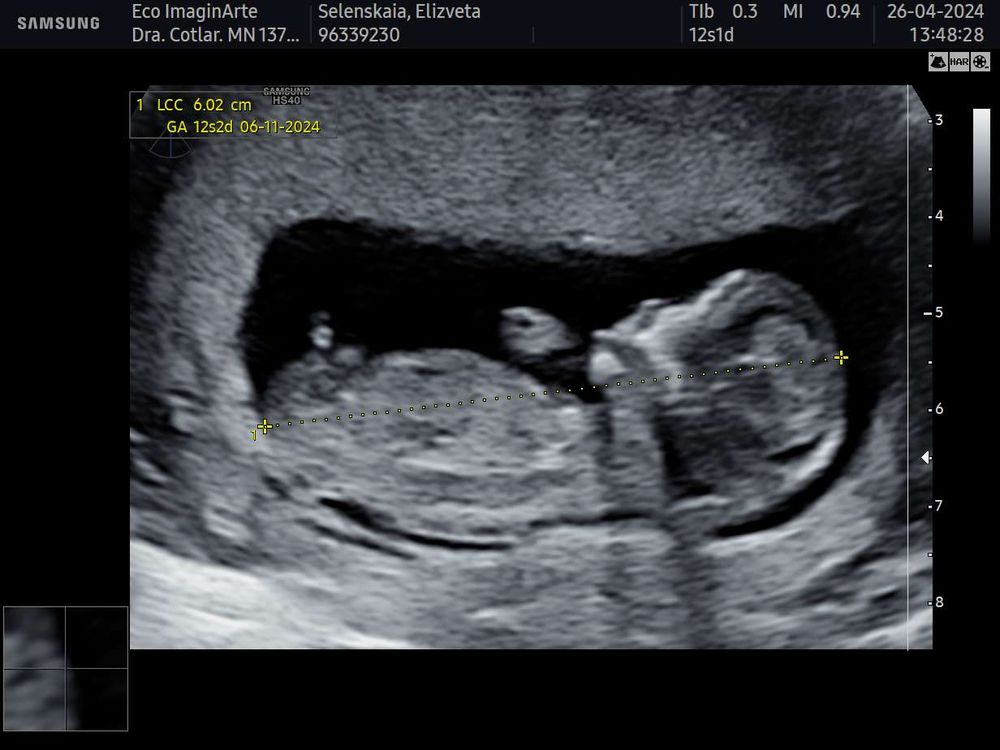

Пол в 15 недель 2 дня, мальчик?

Врач сказала , что пол увидела и написала на бумажке для тортика. В итоге узнали, что у нас мальчик (на первом скриннинге тоже уж больно был половой бугорок похож на мальчишечий - фото с первого УЗИ тоже прикрепляю)

Но вот смотрела я видео и фото с 15 недель и так и не поняла - это оно или не оно (кадры будто сверху, а не снизу) и не могла же врач ошибиться на таком сроке и уверенно так записать для гендер пати мальчика😂 Дочку до второго скриннинга не видели (пряталась)